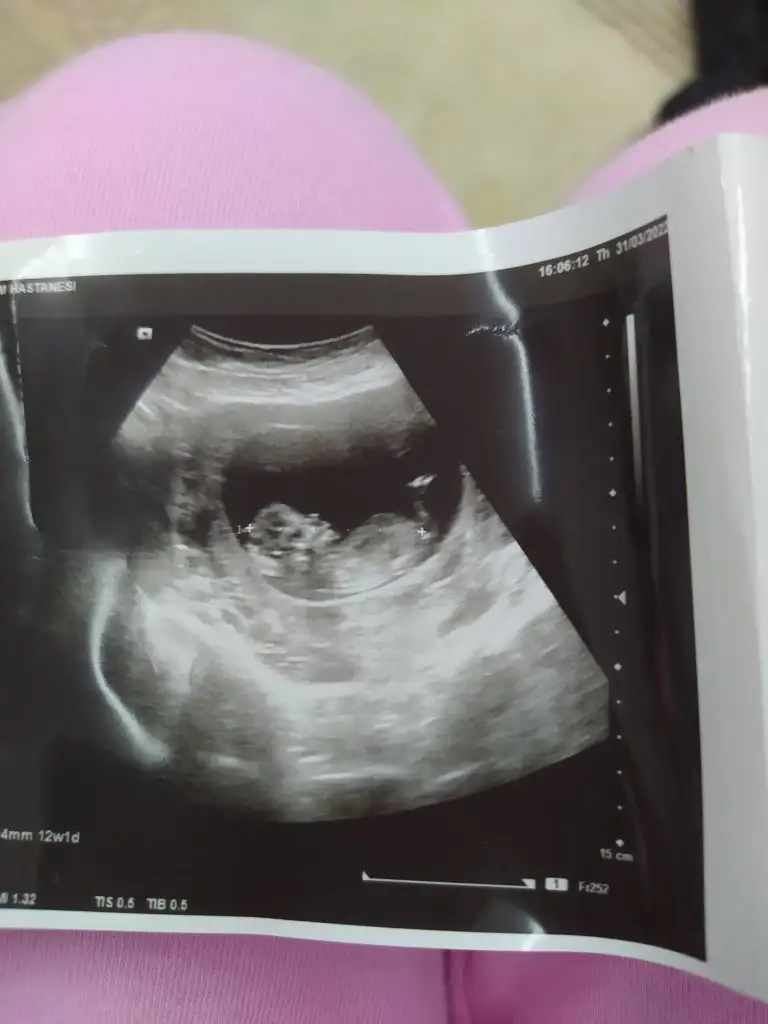

Banada bakarmisiniz ben anlamadim pek 13 hafta burdaEki Görüntüle 3020419 nub teorisine aciklayan Bir resim bu.

Siz kendini de karsilastirabilirsiniz.

Bana bebeginiz kiz gibi geldi